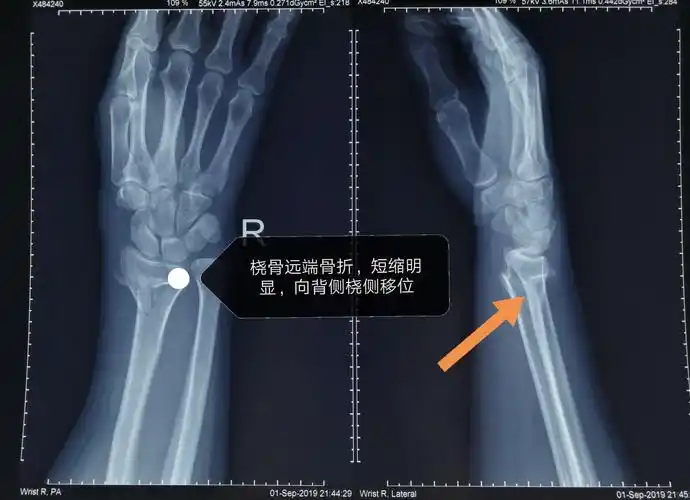

典型的colles骨折